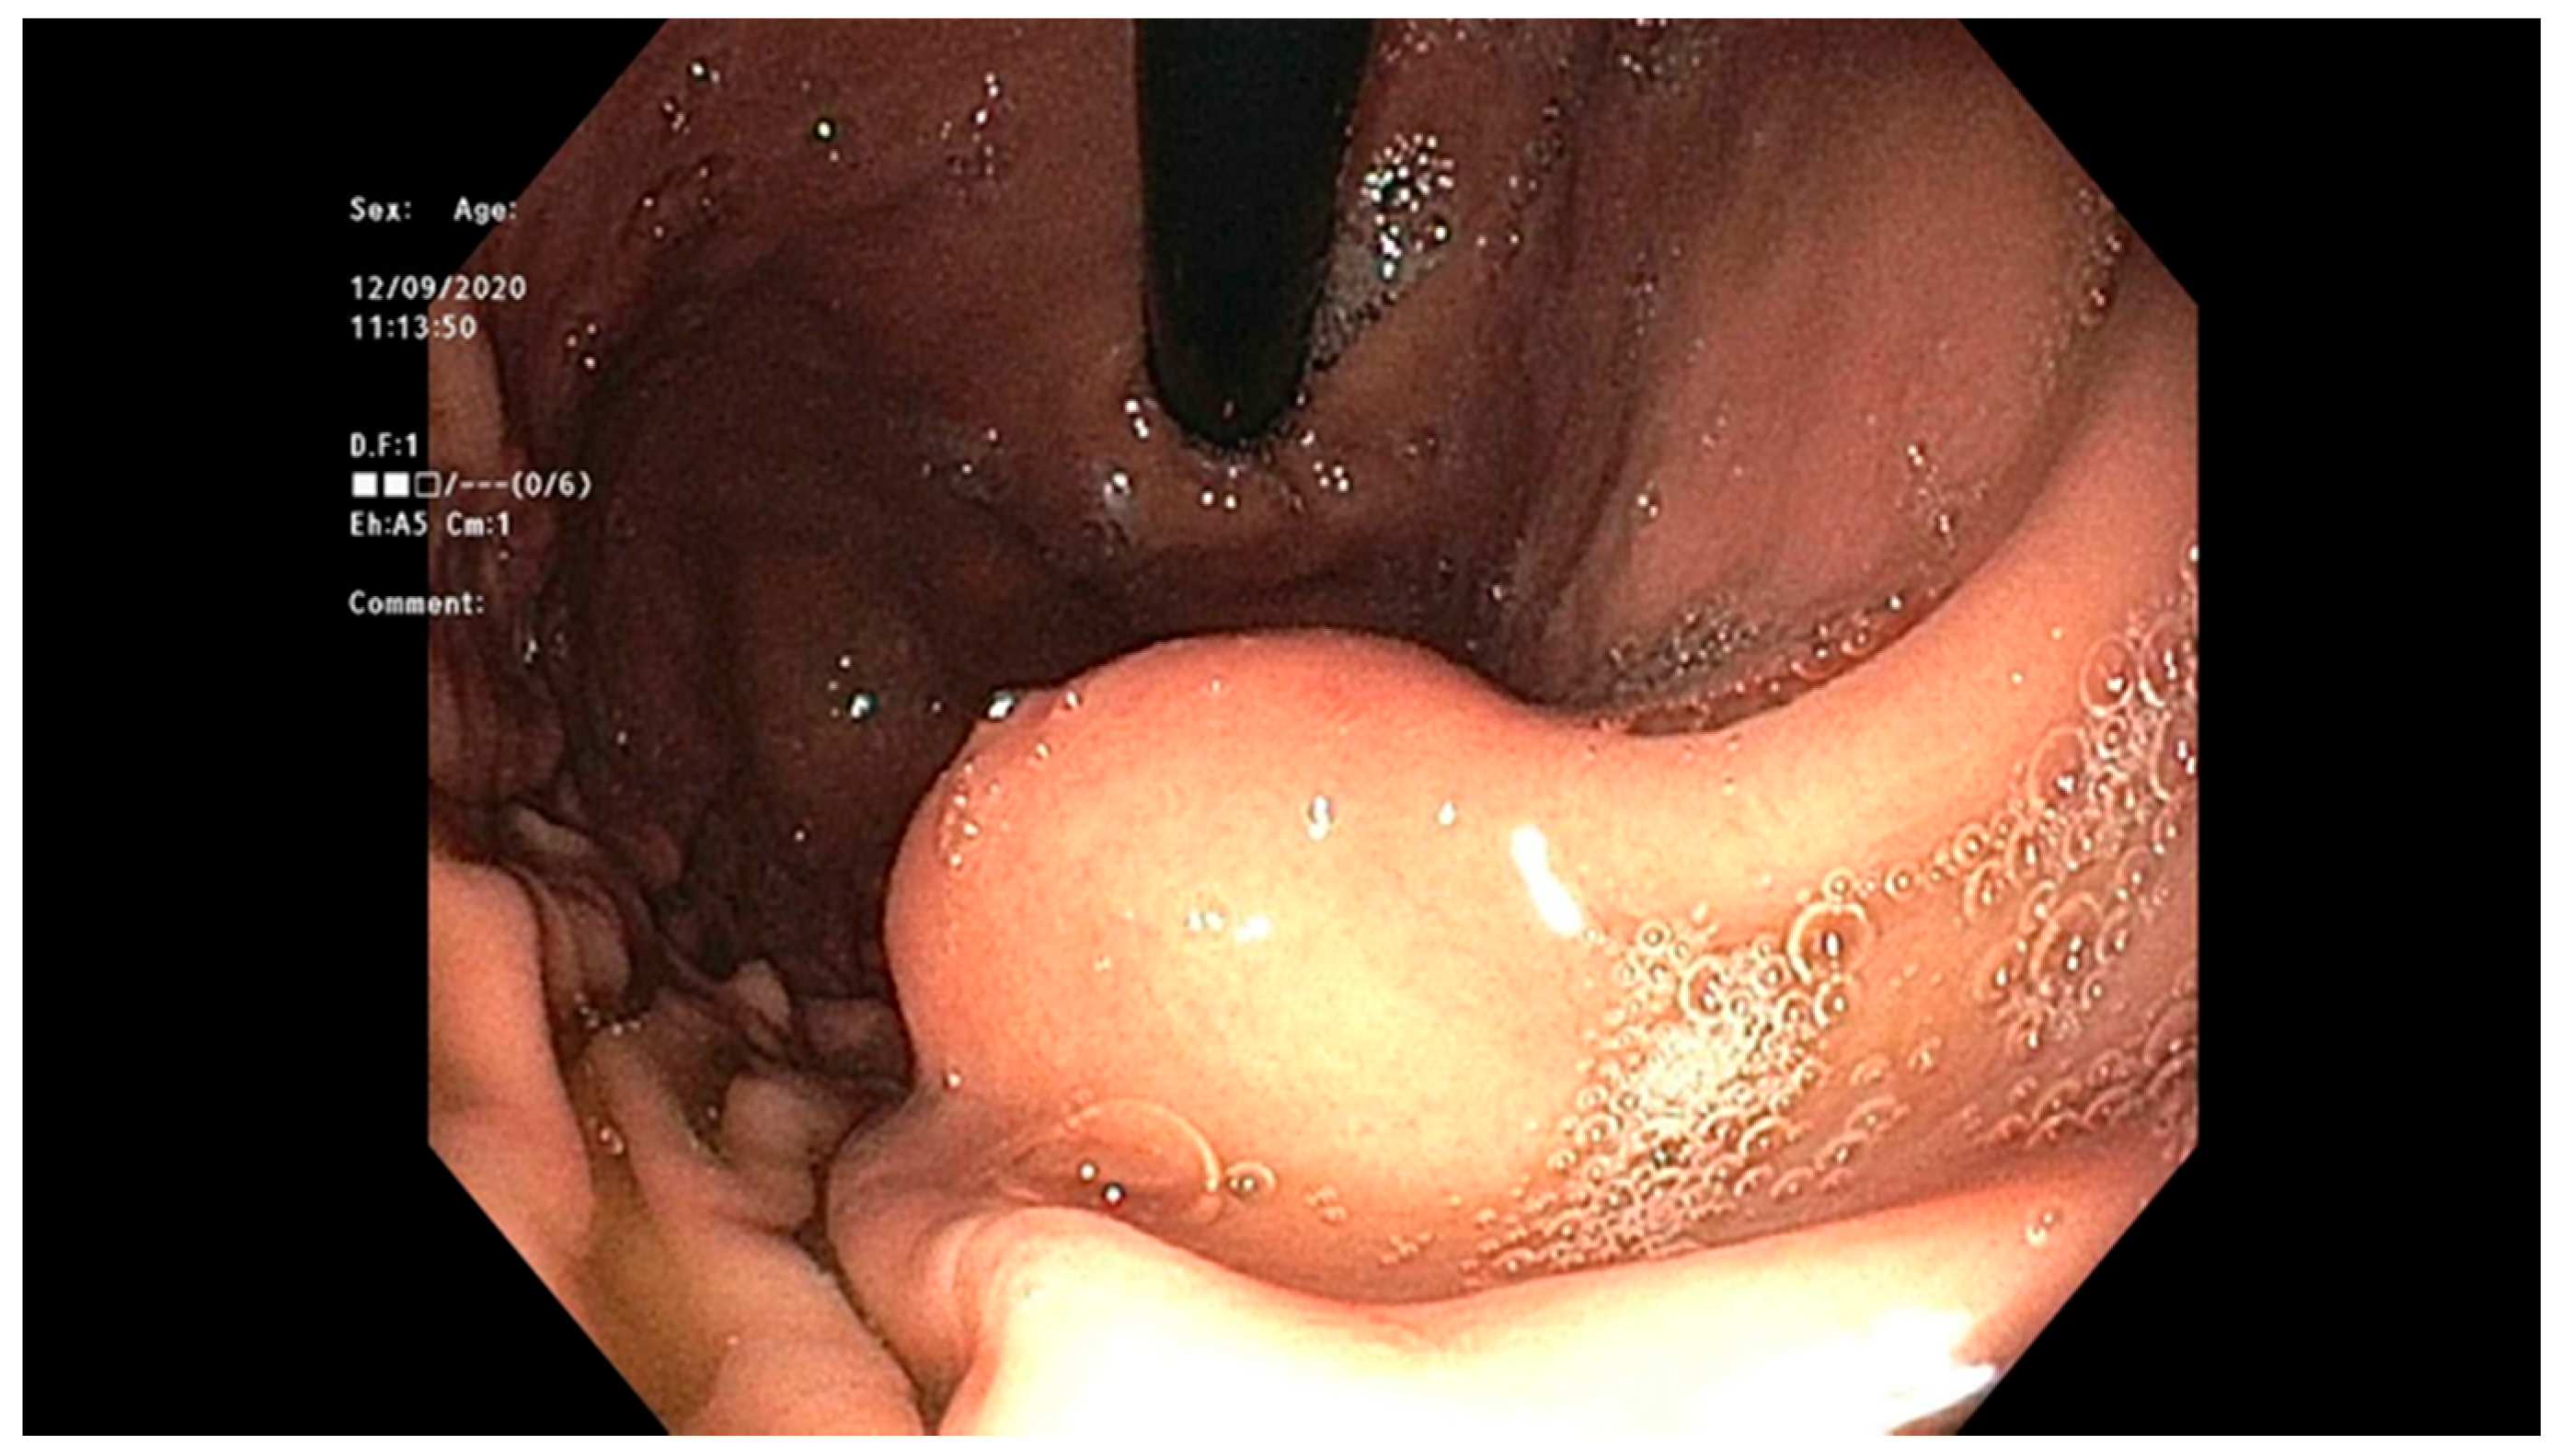

4.2. Early Gastric Cancer (EGC)

4.4. Gastrointestinal Stromal Tumor (GIST)